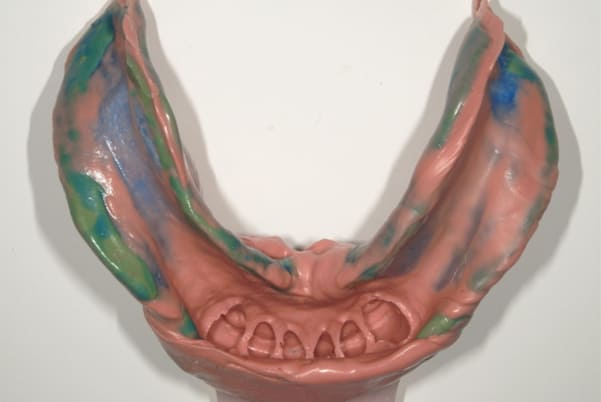

下顎治療前

-

下顎治療後

治療前の入れ歯の奥歯は、治療後の義歯と比較しても分かるように、歯が削れ平らになった状態です。

これにより奥歯のかみ合わせは低くなり、前歯のみが強くあたり、かみ合わせにより上の前歯大きな負担がかかっていたことにより、上の前歯が折れたことが考えられます。

精密な型どりは、通常保険治療では使用しない、この患者様だけに合った型を取るトレーを作製、また寸法変化の最も少ない精密なシリコンを用いてお口の中を精密に限りなく再現する型どりの方法で型をお取りしました。